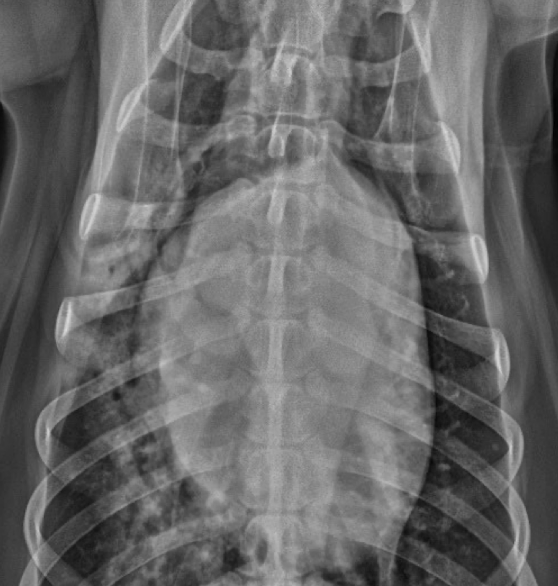

Lung Pattern?

A

Alveolar

Border effacement

How well did you know this?